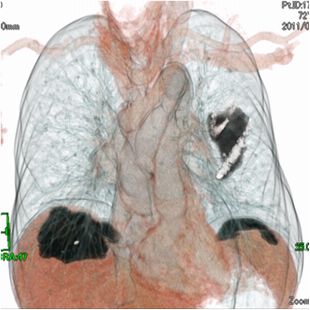

高精度画像診断技術

当院では、各種画像診断装置を導入し、主に各種悪性腫瘍を対象に画像診断、内視鏡的治療、画像介入性低侵襲治療(血管内治療など)、外科的治療に幅広く取り組んでいます。

目的に合った低侵襲な画像診断検査を行い、がんの早期発見および治療に努めています。